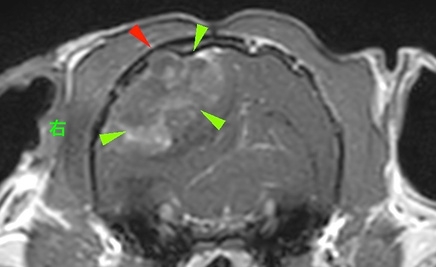

<症例情報> 小型犬雑種去勢雄 10歳主訴:頻回の発作があり来院→頭部の精査のためにMRIを実施 <検査結果>[caption…